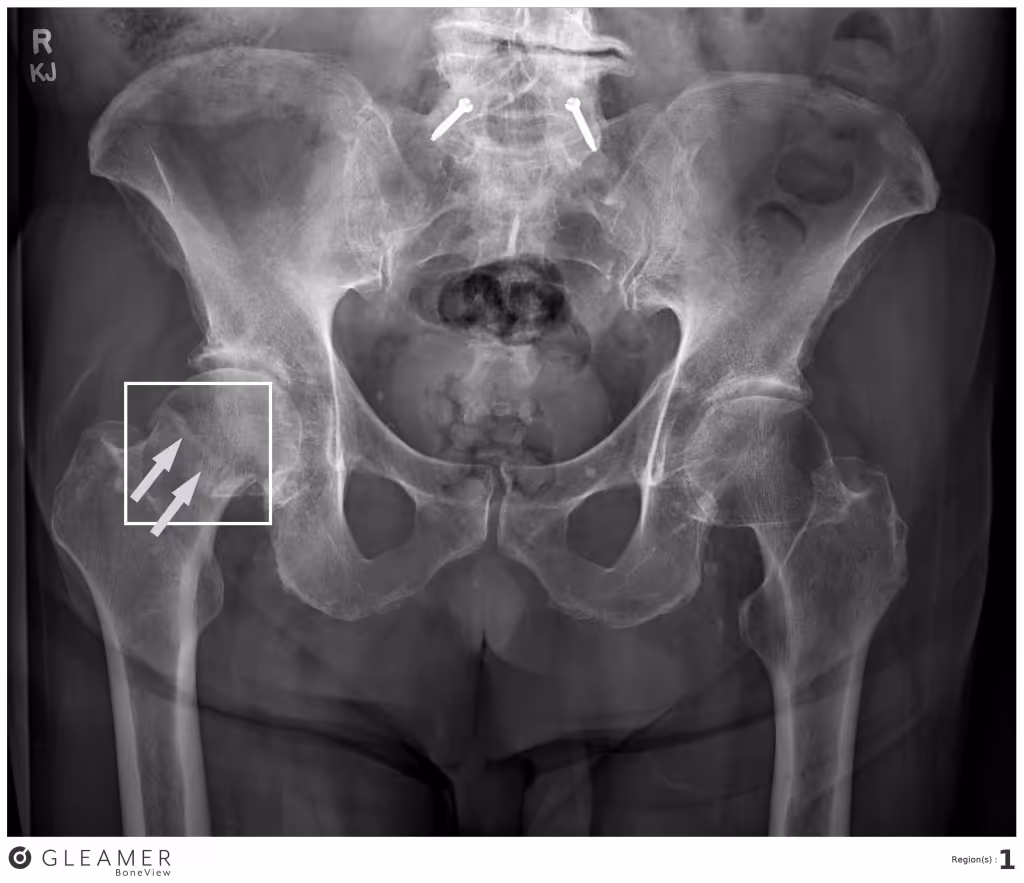

This x-ray shows a single true-positive fracture of the right femoral neck (arrows). AI detected this fracture. One senior and one junior radiologist, two emergency department physicians, one physician assistant, three rheumatologists, and one family medicine physician missed the fracture.

“Although femoral neck fractures are often caught by clinicians, in a busy clinical workflow with several images to read, these fractures can be missed,” said Tran. “This is the importance of AI – it can serve as a second read on every scan and vastly improve health equity for all patients.”